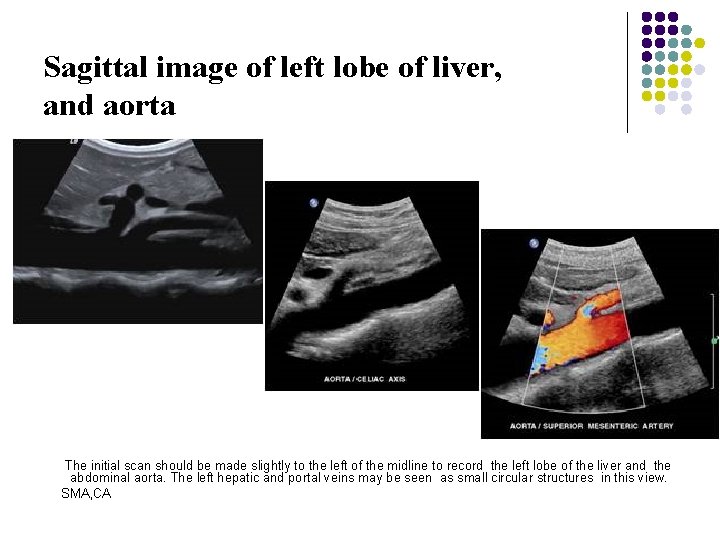

Longitudinal Scan Plane l Scan Ⅰ The initial scan should be made slightly to the left of the midline to record the left lobe of the liver and the abdominal aorta. The left hepatic and portal veins may be seen as small circular structures in this view.

Sagittal image of left lobe of liver, and aorta The initial scan should be made slightly to the left of the midline to record the left lobe of the liver and the abdominal aorta. The left hepatic and portal veins may be seen as small circular structures in this view. SMA, CA